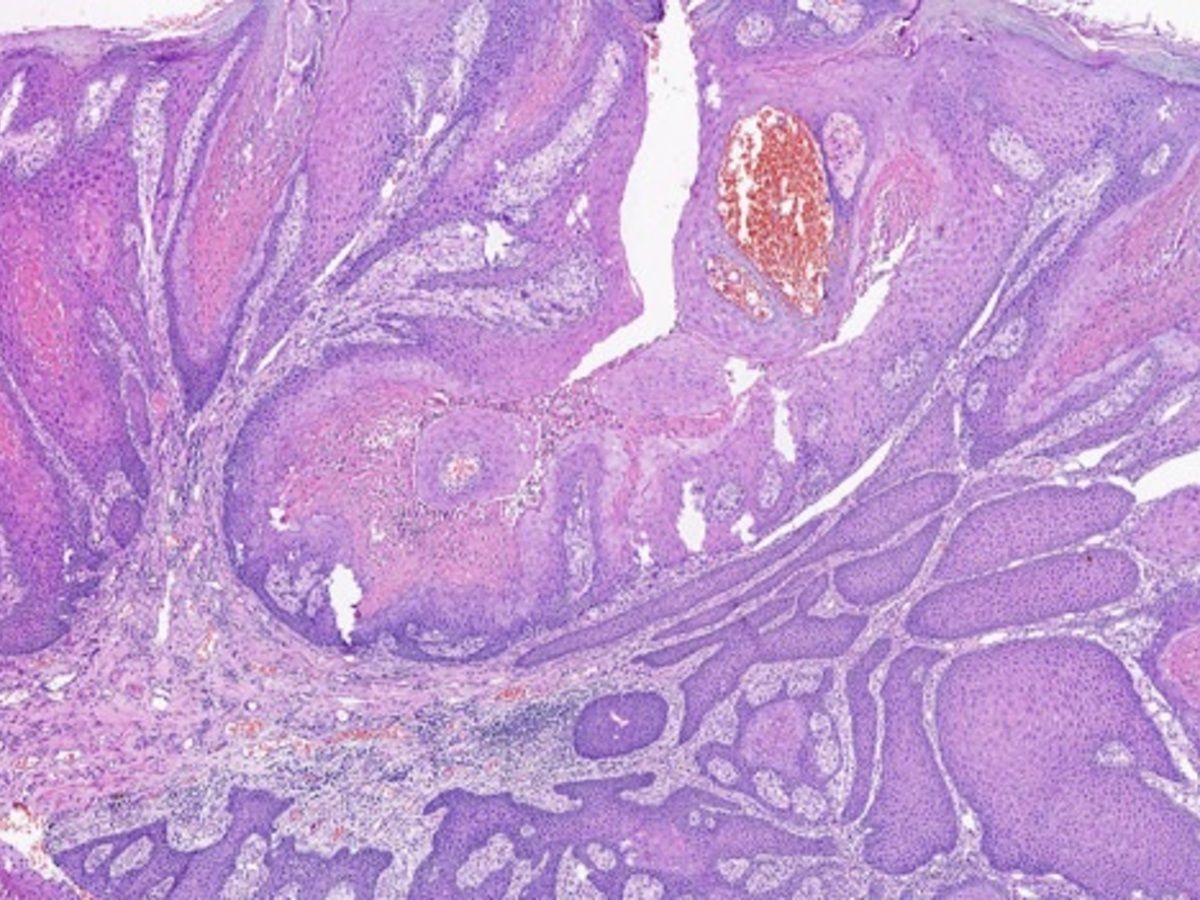

Verruciform Xanthoma - Mayo Clinic Proceedings

image size: 2242x1599